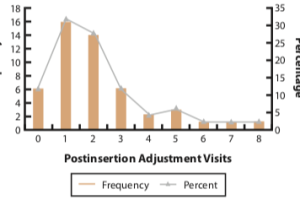

CLINICAL PERFORMANCE OF CAD-CAM-FABRICATED COMPLETE DENTURES: A CROSS-SECTIONAL STUDY

Paola C. Saponaro, DDS, MS,a Burak Yilmaz, DDS, PhD,b Reza H. Heshmati, DDS, MPH, MS,c and Edwin A. McGlumphy, DDS, MSd. Purpose. The purpose of this retrospective study was to evaluate clinician experience with digital CD fabrication attempted in a 2-visit protocol. The actual number of appointments required for insertion and the number of postinsertion adjustment visits, and whether the incidence of treatment complications was related to operator experience were recorded and evaluated.